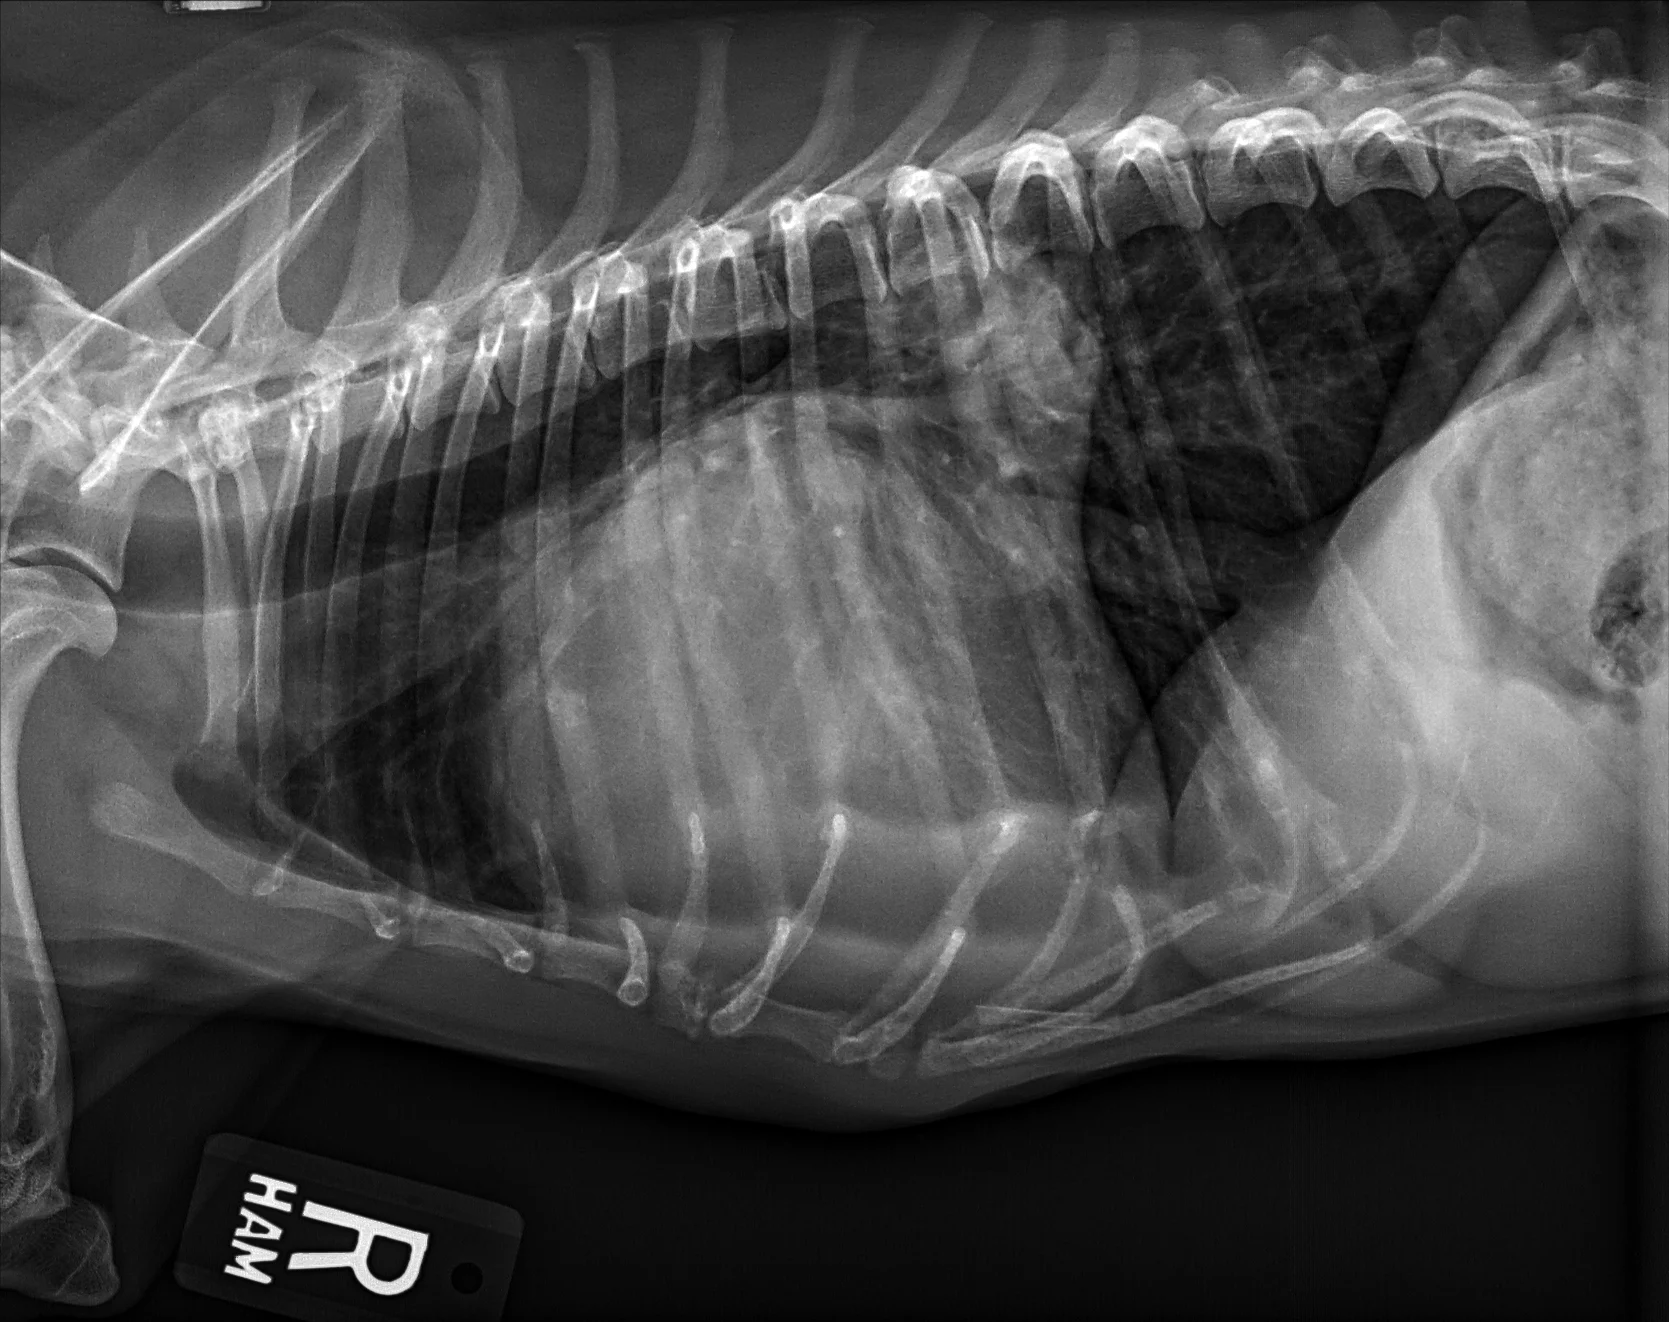

At least 2 orthogonal views, ideally taken during peak inspiration, are necessary for appropriate radiographic study of the cardiovascular system; however, a 3-view study is ideal for comprehensive evaluation of the thorax. Some differences should be considered when deciding to acquire a right versus left lateral projection and a dorsoventral (DV) versus ventrodorsal (VD) projection. On the left lateral view, the cardiac silhouette is typically more rounded and the apex is further elevated from the sternum than in the right lateral view (Figure 1). In the DV view, the cardiac silhouette is commonly displaced cranially and to the left by the diaphragm and appears more rounded than in the VD view. The caudal pulmonary vasculature is better delineated in the DV view, whereas the lung field (particularly the accessory lobe) is better evaluated in the VD view (Figure 2).

FIGURE 1 Normal right and left lateral projections of the thorax in a large, crossbreed dog. The difference in the cardiac silhouette and the apex elevation (arrow) from the sternum in the left lateral view can be seen. VHS, VLAS, modified VLAS (M-VLAS), and VRHi collected from the right lateral view are 10.6, 1.7, 2.8, and 3, respectively, and 10.6, 1.5, 2.9, and 3.4, respectively, collected from the left lateral view. Given these differences, serial radiography should be performed using the same lateral view if only one view is used. In some dogs, roundness of the cardiac silhouette in the left lateral view can be pronounced and misinterpreted as right-sided heart enlargement, particularly if compared with a prior right lateral view. Images courtesy of Federico Villaplana Grosso, DACVR, DECVR